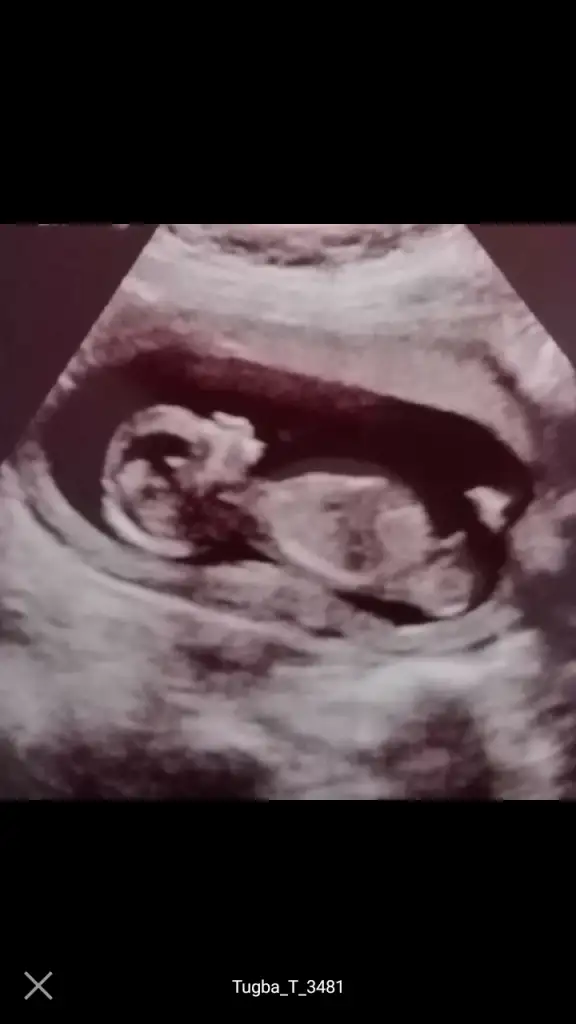

dr soylemeden siz gorun genital nub teorisi ( bebegin cinsiyeti)

O gözüken nub mu emin olamadım ama yine de bir atayım belki fikir yürüten olur didimm.

10+5 günlük bir kurbağa 🐸 🐣

Ne dersiniz?? Ikra meyra Ikra meyra